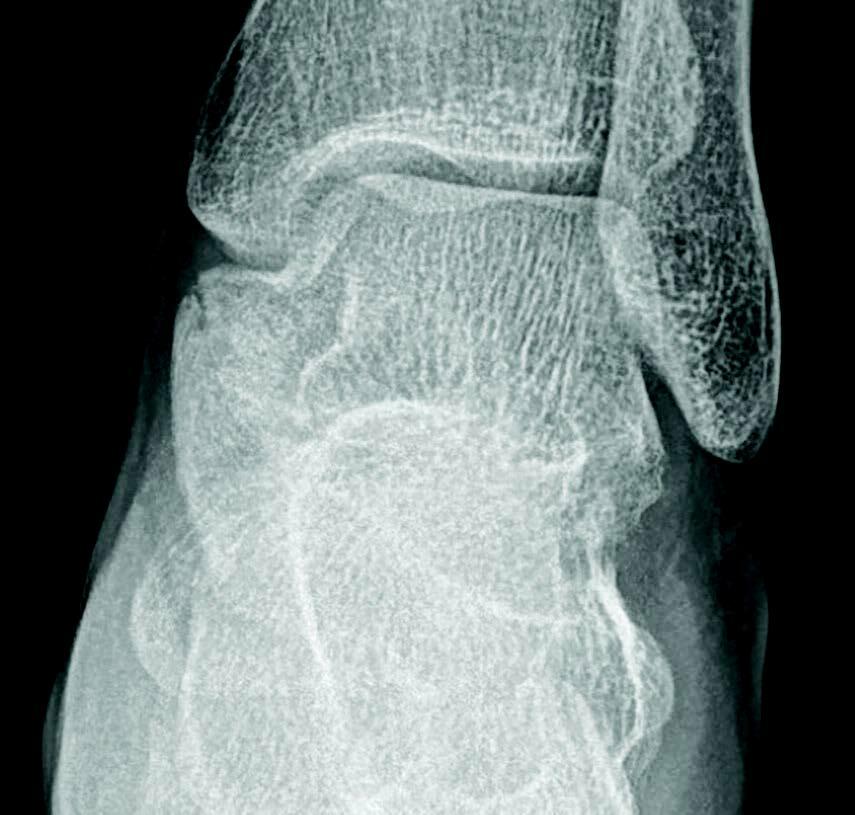

A tarsal coalition exists when there is a congenital, complete or incomplete union between two or more tarsal bones causing restricted motion or absence of motion. Tarsal coalitions remain challenging for the foot and ankle physician and surgeon. Their clinical hallmarks are primarily pain, rigid pes valgus and/or rigid pes planus deformity, and often tonic peroneal muscle spasm. Although the diagnosis of a tarsal coalition is often readily apparent upon clinical examination, diagnostic imaging is confirmatory and often aids in planning any necessary surgical intervention. Sequentially, the author always obtains radiographs of the involved foot first followed as necessary by advanced imaging with either computerized tomography (CT) or magnetic resonance imaging (MRI) scans, or in some instances of incomplete tarsal coalition, both CT and MRI.1

Recently, the literature presents arguments for the inclusion of the size and type of talocalcaneal coalition, and the degree of heel valgus as factors to consider when deciding between joint resection and joint fusion.3-11 Some hypothesize that the size of a talocalcaneal coalition inversely correlates with the success rate of resection, and some researchers used preoperative advanced imaging studies, particularly CT, to investigate.3,4 Arbitrarily, based only on their personal experience, these investigators concluded that talocalcaneal coalitions involving greater than 50 percent of the talocalcaneal joint are less amenable to surgical resection.3,4 More recently though, several authors challenged this subjective assumption and instead determined that no definitive talocalcaneal coalition size precludes an attempt at resection in every patient.5-7

Additionally, different described shapes and morphologies of talocalcaneal coalitions may be a factor to consider when debating arthroplasty or arthrodesis. In 2010, Rozansky and colleagues used thin-cut 2D and 3D CT scans to divide talocalcaneal coalitions into five different types based on their cartilaginous or bony nature, location and facet joint orientation.8 In 2016, Bixby and associates used CT scans to assess 97 patients with a total of 138 talocalcaneal coalitions.9 They found that 97 (70 percent) of the coalitions involved the middle facet, 39 (28 percent) the posteromedial aspect of the joint and two (1.4 percent) involved the posterior facet.9 They described the posteromedial talocalcaneal coalition as being associated with an intact, but shorter middle facet with a long sustentaculum tali.9